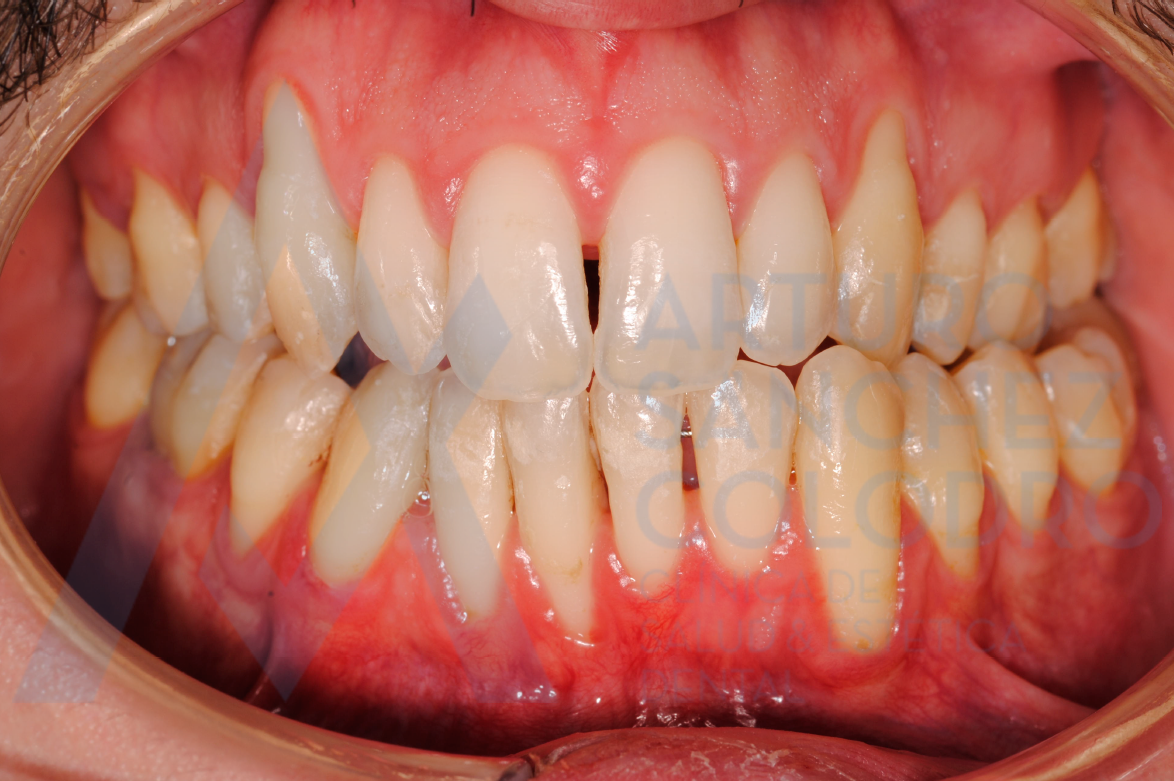

Estas son las imágenes obtenidas de exploración intraoral inicial: